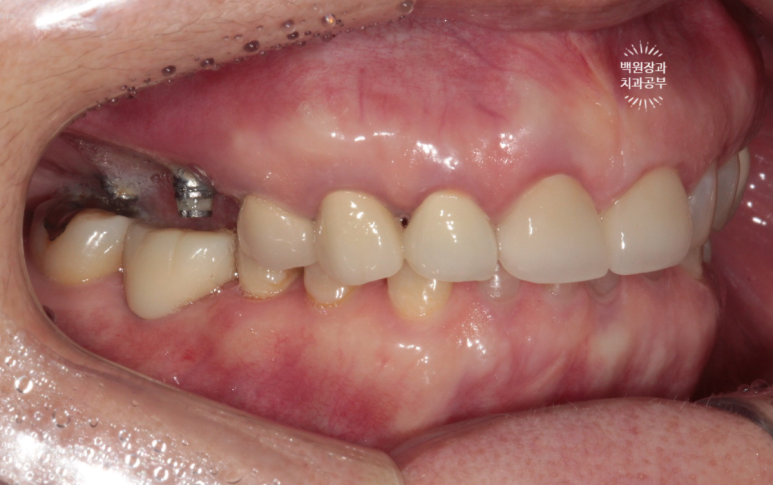

금색의 locator가 장착된 임플란트의 주변에 고름이 맺혀있는게 보이시나요..?

네개의 임플란트 모두 상당한 임플란트주위염에 시달리고 있는 것을 볼 수 있었습니다.

약 20년 전에 제작한 오른쪽 위 외산 임플란트에서 고름이 나온다는 주소로 내원한 70대 여자 환자분이었습니다.

임플란트는 아마도(?) 브레네막(Branemark) 임플란트로 생각되는데, 당시에는 최고의 명품이었죠.

여튼, 좋지 위치에 식립되어 있는 임플란트도 아니었고, 임플란트 주위염이 심하여 농이 나오는 상태였기 때문에 임플란트를 제거하기로 하였습니다.

또 다른 이유로 잘못 식립된 임플란트의 위치 때문에, abutment(=지대주)가 너무 짧아 임플란트 크라운이 자주 탈락하는 상태였어요. 기둥이 두껍고 길어야 보철물이 잘 붙어있을텐데 말이죠...?